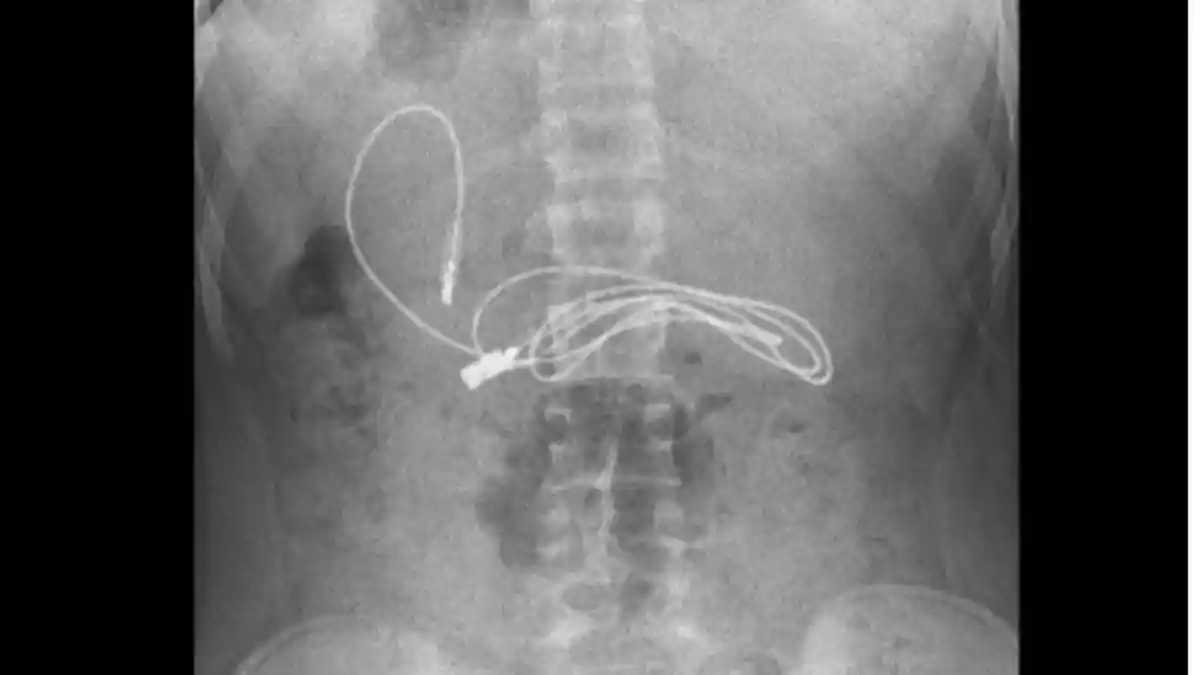

Sang remaja pun langsung dirontgen. Dokter kemudian melihat adanya benda asinalam organ pencernaan sang remaja ini.

Sang remaja pun langsung dirontgen.

Dokter kemudian melihat adanya benda asinalam organ pencernaan sang remaja ini.

Benda asing ini tak lain dan tak bukan adalah kabel pengisian daya atau charger ponsel.

Ahli gastroenterologi, Yasar Dogan ini pun serukan prosedur endoskopi untuk keluarkan kabel di perut remaja ini.

Benda asing ini disingkirkan lewat prosedur endoskopi.